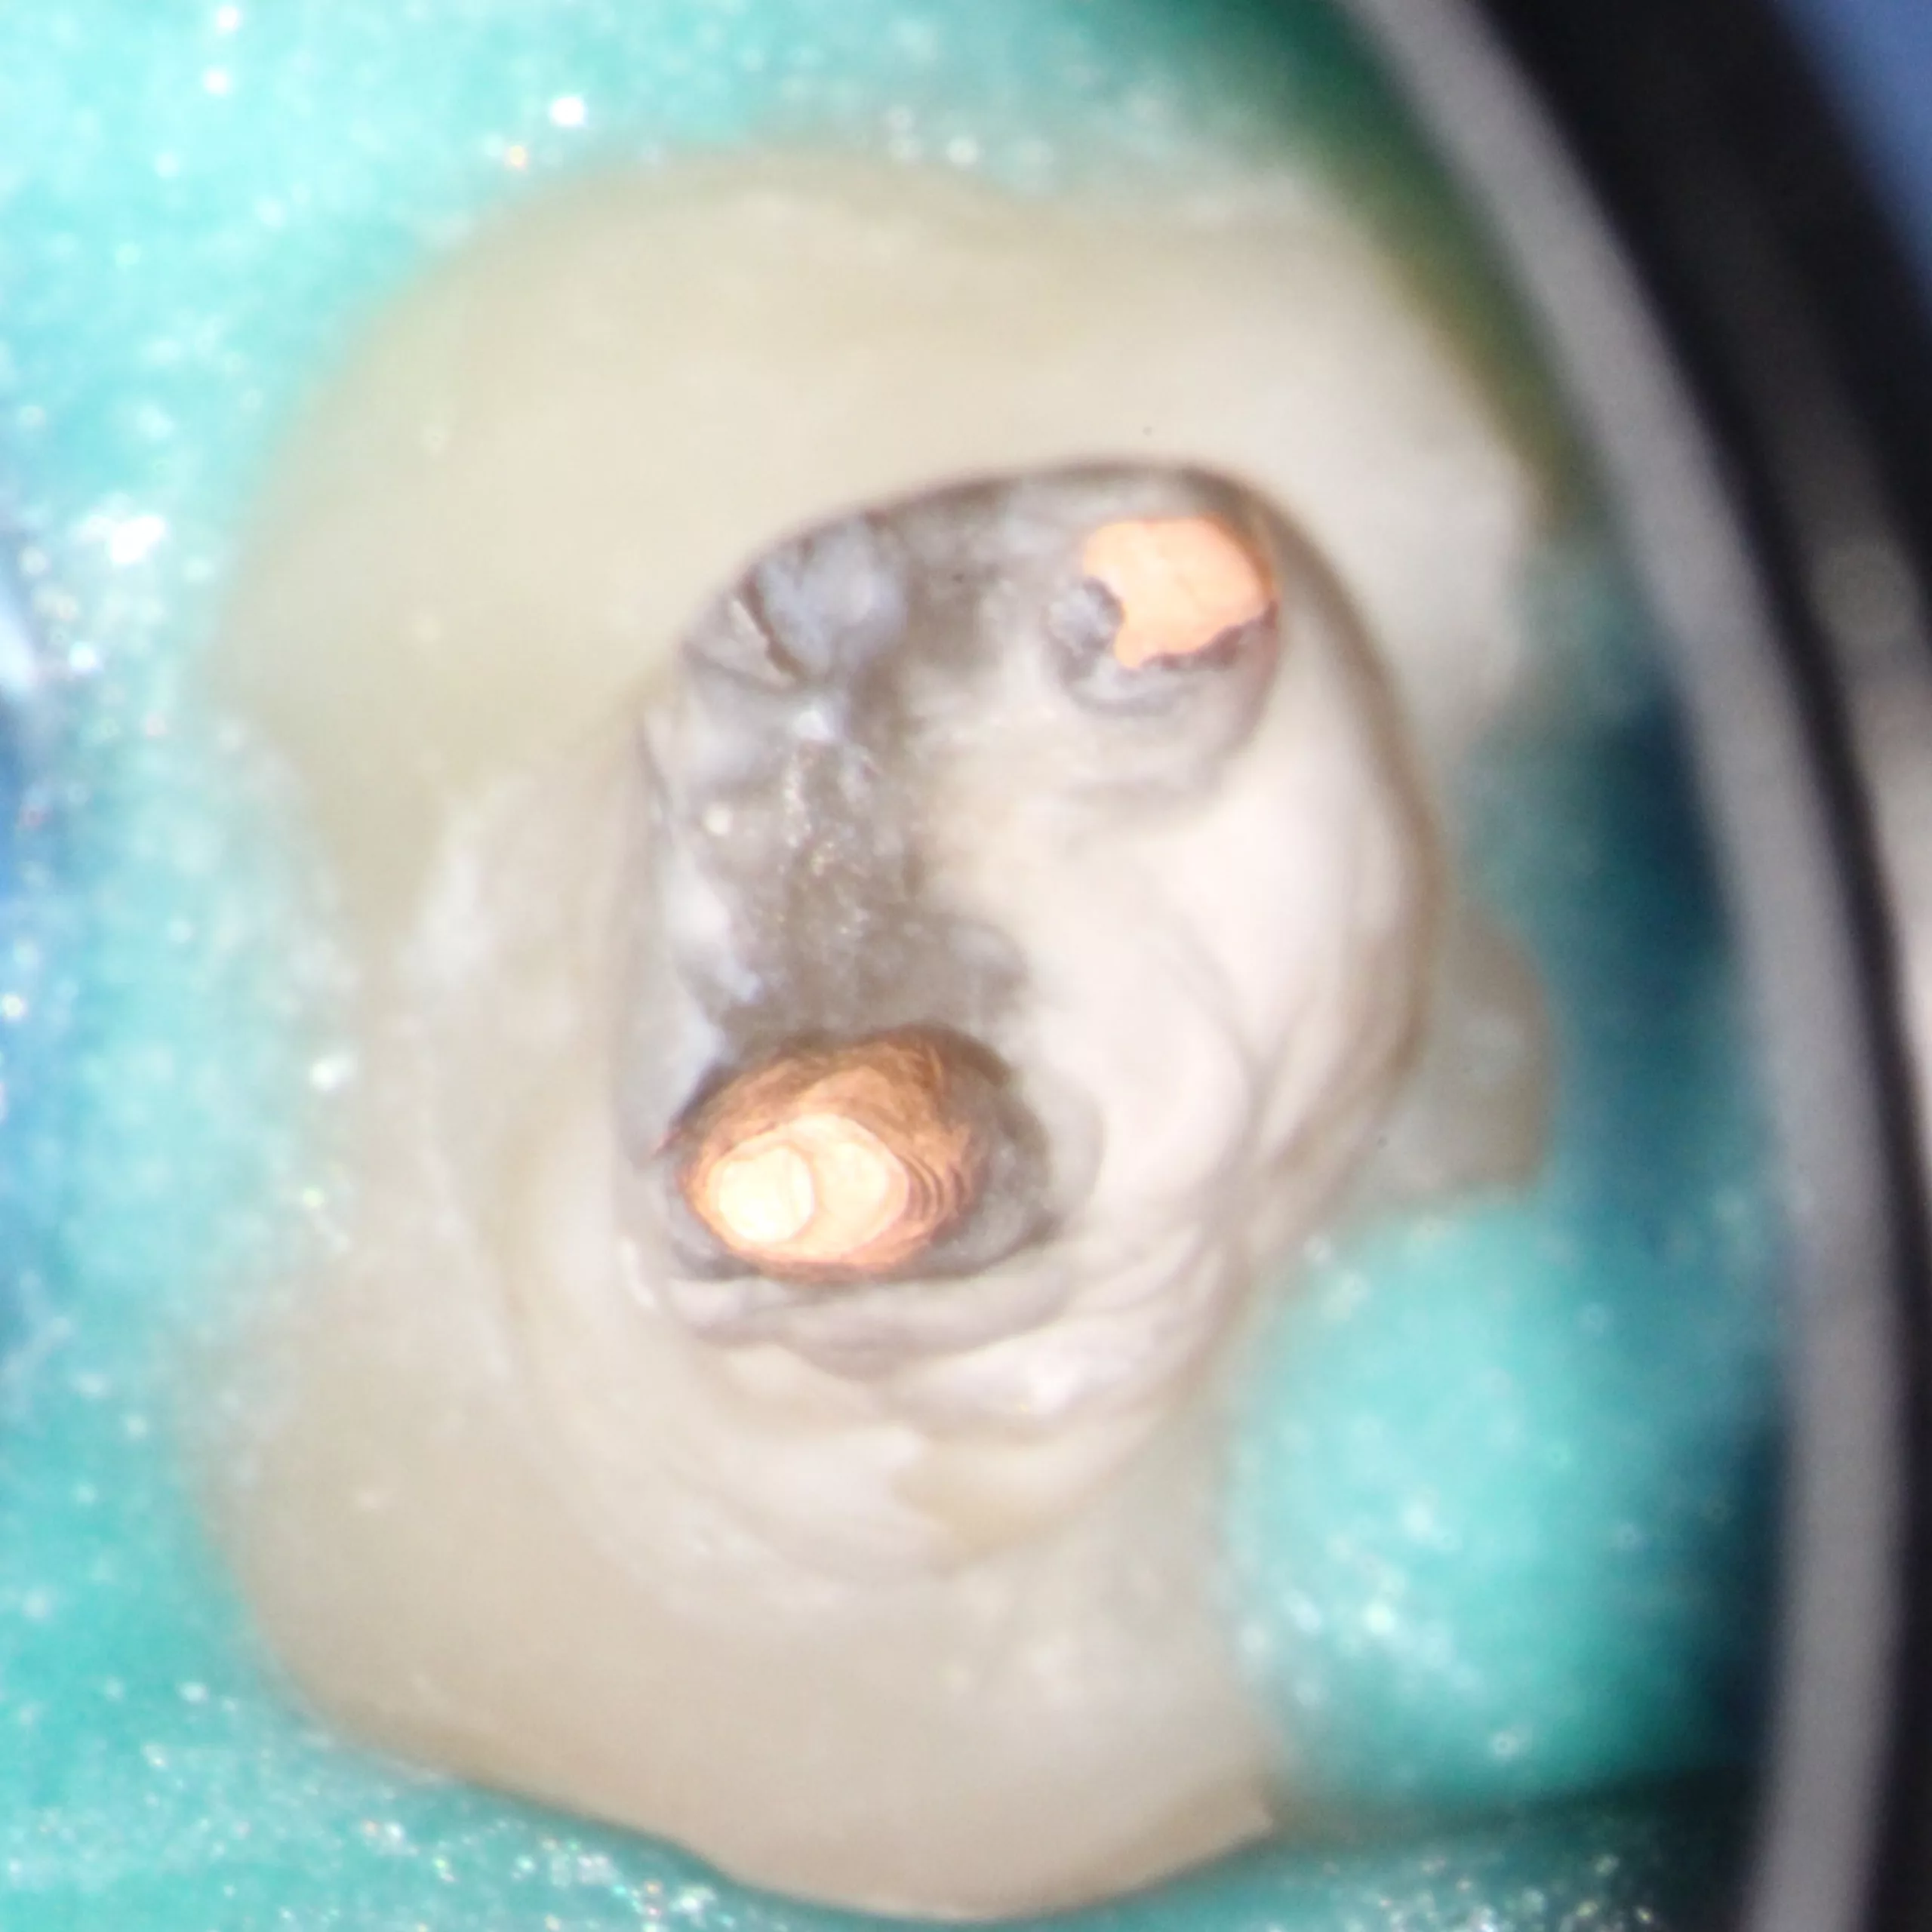

Die Abbildung 54 zeigt das Kanalsystem unmittelbar vor der Wurzelkanalfüllung, die Abbildung 55 nach der vertikalen Kondensation des Wurzelfüllmaterials. Um eine weitere Schwächung des Wurzeldentins zu vermeiden, favorisieren wir eine passive Stiftinsertion ohne weitere Stiftbettpräparation. Auch bzw. insbesondere, wenn ein Zahn mit einem Stift-Stumpf-Aufbau versehen werden soll, sollte ein zusätzlicher Hartgewebsverlust möglichst vermieden werden, der die Prognose des Zahnes zusätzlich verschlechtern würde [17,33,88,93]. Die Schlussfolgerung aus den angeführten Studien ist, auf eine Stiftbohrung zu verzichten, wenn ein Wurzelkanal im koronalen Drittel weit und gerade genug ist, um einen Stift aufnehmen zu können. Dies gilt insbesondere für Seitenzähne, die eher einer axialen Belastung ausgesetzt sind, und ist nur möglich, wenn der Stift unmittelbar nach der Wurzelkanalfüllung eingebracht wird.

Die Abbildung 56 zeigt die Einprobe eines Glasfaserstiftes (EasyPost, Dentsply Sirona). Nach Vorbehandlung des Stiftes mit dem Visalys Restorative Primer und nach Reinigung des Kanalsystems mit AH Cleanser (Dentsply Sirona) sowie der Applikation des Visalys Tooth Primers im Zahn erfolgte die zeitgleiche Verklebung des Glasfaserstiftes mit Visalys CemCore (diesmal in der opaken Variante) und dem internen Aufbau des gesamten Zahnes. Die Abbildungen 57 bis 59 zeigen das 2-schichtige Einbringen von Visalys CemCore Opaque nach einer Zwischenhärtung des 1. Inkrements für 40 Sek., die Abbildung 60 die Röntgenkontrolle der Wurzelfüllung und des Stumpfaufbaus. Der okklusale Anteil der Kavität wurde wenige Minuten später von einem Kollegen okklusal reduziert und mit einem klassischen lichthärtenden Komposit definitiv versorgt.